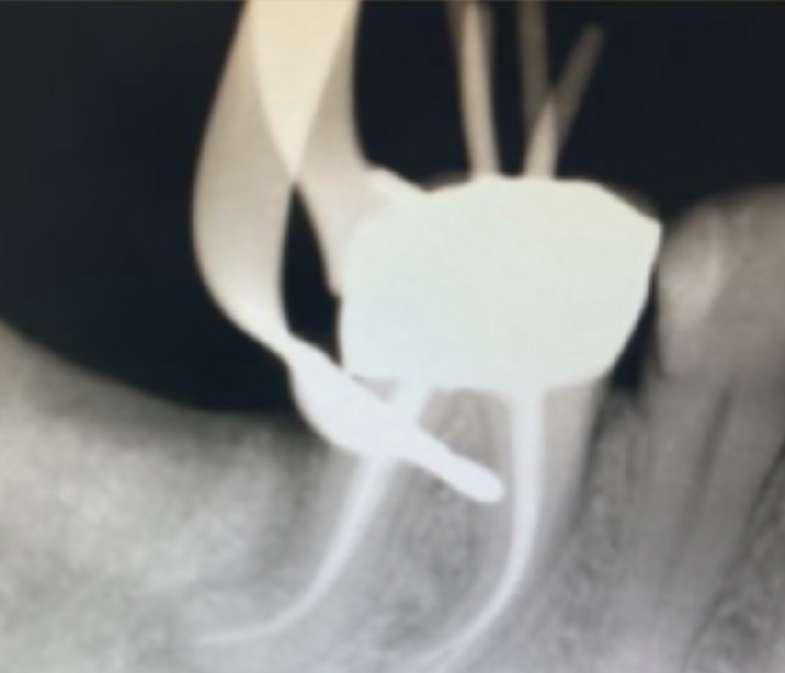

Eine 42-jährige Patientin kam in die Praxis und klagte über einen Kronenbruch und starke Schmerzen im linken unteren Seitenzahnbereich. Die intraorale und röntgenologische Untersuchung ergab eine disto-okklusale Karies in Zahn 36 (Abb. 1) und eine Freilegung des distalen Pulpahorns. Der Zahn war beim thermischen Kältetest sehr empfindlich; es wurde eine akute Pulpitis diagnostiziert und eine endodontische orthograde Behandlung vorgeschlagen und akzeptiert. Nach einem minimal-invasiven Zugang wurde die Zugangskavität ausgehend vom distalen Teil des Zahns gestaltet, um einen unnötigen Verlust von Zahnhartsubstanz zu vermeiden. Eine solche Entscheidung war ein Kompromiss zwischen den Vorteilen eines breiteren, geradlinigen Zugangs (der bei komplexen engen Krümmungen wie im vorliegenden Fall ideal ist) und den Nachteilen einer Schwächung der Restzahnsubstanz: Der mesiale Rand war intakt und es wurde entschieden, ihn nach minimalinvasiven endodontischen Protokollen zu erhalten.

Außerdem ist ein ideales geradliniges Einbringen von endodontischen rotierenden Nickel-Titan(NiTi)-Instrumenten nicht immer möglich, wenn ein Molar wie im vorliegenden Fall leicht nach distal geneigt ist. Komplexere Wurzelkanalkonfigurationen (d. h. wenn, wie in diesem Fall, zusätzliche Kanäle vorhanden sind) erfordern mehr Aufmerksamkeit bei der Planung eines angemessenen endodontischen Zugangs, um alle verschiedenen Öffnungen richtig zu erreichen.

Infolgedessen war sich der Kliniker bewusst, dass rotierende NiTi-Instrumente aufgrund des Vorhandenseins mehrerer Krümmungen einer hohen Biegebelastung ausgesetzt sein würden, was außerdem Flexibilität erforderte, um iatrogene Fehler zu vermeiden. Daher war das erste Kriterium die Auswahl extrem flexibler, wärmebehandelter martensitischer NiTi-Instrumente mit Controlled-Memory-Effekt; das zweite war die Auswahl von Instrumenten mit variabler Konizität, um den TaperLock- und Einschraubeffekt zu minimieren; das dritte Kriterium war die Auswahl von Instrumenten mit ausreichender Metallmasse, um Torsionsbelastungen in engen Kanälen standzuhalten. Die Wahl fiel auf EdgeTaper Platinum (ETP) von EdgeEndo, Albuquerque, NM, das alle erforderlichen Eigenschaften erfüllte; sehr widerstandsfähige und flexible Instrumente, die leichter verformt werden können als Feilen der Wettbewerber und die die gegebene Vorkrümmung beibehalten, was ein einfacheres Einführen ermöglicht und die Notwendigkeit einer breiteren Zugangskavität minimiert.

Nach Legen eines manuellen Gleitpfads mit K-Feilen aus Edelstahl bis Größe 15 und einer Arbeitslängenbestimmung mit einem elektronischen Apex-Locator wurden ETP-Instrumente in folgender Reihenfolge verwendet: S1, S2, F1, F2. Alle Instrumente erreichten die volle Arbeitslänge, wobei sie sanft mit 300 U/min (und 2 N Drehmoment) gedreht wurden, um eine Überlastung zu vermeiden. Zwei entscheidende operative Parameter wurden gewählt: Zuerst wurden die Instrumente während der Einwärtsbewegung langsam und schrittweise vorgeschoben (nicht mehr als 1-2 mm Vorschub pro Schritt) und nach jedem Schritt wurden sie aus den Kanälen entfernt, die Furchen gereinigt und eine Spritzenspülung durchgeführt.

Der zweite Parameter war die Verwendung der Auswärtsbewegung, um das koronale Aufweiten zu verbessern. Dies hätte mit dem gleichen ETPInstrument erfolgen können, jedoch wurden für die S1- und S2-Instrumente etwas steifere EdgeTaper (ET)-Rotationsinstrumente gewählt. ETInstrumente haben das gleiche Design wie ETP, sind aber nicht wärmebehandelt, was sie etwas steifer und effizienter beim Schneiden macht. Daher ermöglichten ET S1 und S2 (verwendet nach ETP S1 bzw. S2) ein schnelleres und besseres koronales Aufweiten. Sie wurden nur mit einer Auswärtsbewegung („Bürsten“), einer erhöhten Drehzahl (500 U/min) und einem reduzierten Drehmoment (1,5 N) verwendet. Durch die Eliminierung koronaler Interferenzen und die Vergrößerung des Kanaldurchmessers haben ET S1 und S2 die apikale Aufbereitung mit ETP F1 und F2 schneller und sicherer gemacht, wie in den DVT-Bildern zu sehen ist (Abb. 2 und 3). Die Auswärtsbewegung erwies sich mit minimalen Torsions- und Biegebelastungen auf die rotierenden NiTi-Instrumente als äußerst sicher, vorausgesetzt, die Instrumente rasten im Kanal nie vollständig ein oder blockieren. Diese neue, innovative Kombination ähnlicher Instrumente (ET und ETP) mit unterschiedlichen Eigenschaften aufgrund eines unterschiedlichen Herstellungsprozesses wird als „hybridisierende Wärmebehandlungstechnik“ bezeichnet und wurde mit den oben

genannten Instrumenten gut durchgeführt. Abb. 3 und 4 zeigen, wie die Kanalgeometrien gut eingehalten wurden; die richtige Formgebung (ausreichende Kanaldurchmesser sind in 3D-Bildern besser zu erkennen, wie in Abbildung 2 und 3 gezeigt) erfolgte schnell und einfach mit einer 45minütigen Wurzelkanalbehandlung in einer einzigen Sitzung, ohne iatrogene Fehler, ohne Verformung oder Bruch der Instrumente. Die Kanäle wurden mit einer Single-Cone-Kalthydrauliktechnik unter Verwendung von Bioceramic Sealer verschlossen, einem Material, das eine einfache und schnelle Lösung bietet.